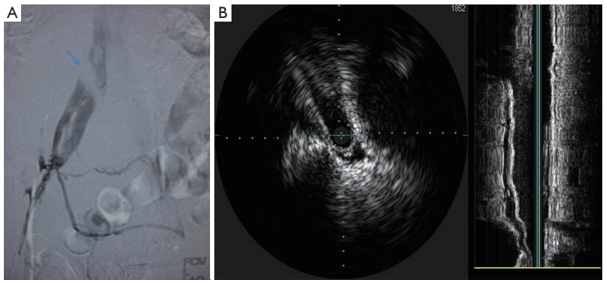

Hình 1: Hội chứng May–Thurner trên chụp tĩnh mạch đồ và siêu âm nội mạch2

(A) Chụp tĩnh mạch xâm lấn chi dưới trái cho thấy động mạch chậu chung phải chèn ép tĩnh mạch chậu chung trái, kèm tuần hoàn bàng hệ; (B) Siêu âm nội mạch xác nhận tình trạng hẹp tĩnh mạch chậu trái.